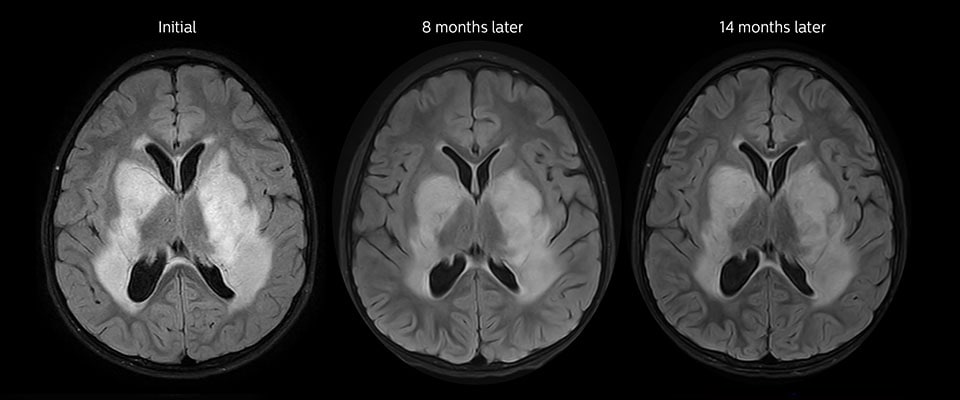

(If data permits), show progression of tumour over time

A video showing the progression of the tumour for multiple patients. I still need to look at how the data varies across patients. The tumours will be shrinking over time, but it will be interesting to see how different patients respond to chemotherapy. I will also include how to identify reliable data for visualisation and how to use the Cancer Imaging Archive to download the relevant data files. I hope to have my project fully portable to the YURT so I can include footage of it running in the YURT.

This could be almost like a timelapse.

If not completed, 3D visualisations of brain with the tumours, so they look something like the visualisation below. Ensure that multiple scans for the same patient are chosen so the progress can be seen.